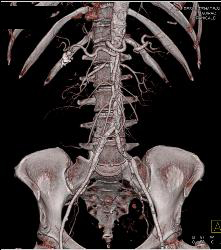

Thigh Hematoma Without Vascular Injury S/p Trauma